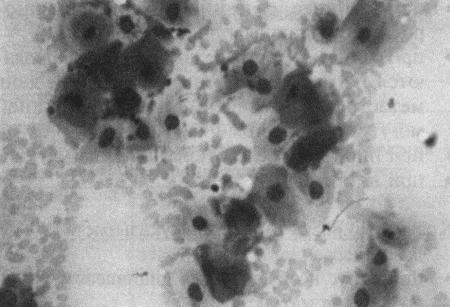

Фиг. 2.2.

Вагинальные выделения кошки (а). Выделения, типичные для фазы эструса. Большая часть клеток представляет собой безъядерные кератинизированные клетки или клетки с пикнотическим ядром. Присутствуют промежуточные клетки (b). Выделения, характерные для метэструса, — «течки», иногда наблюдаемой у кошек в конце эструса. Присутствуют поверхностные и промежуточные клетки, повышено содержание лейкоцитов. Этот короткий метэструс наблюдается в течение 24–48 часов (см. Приложение)